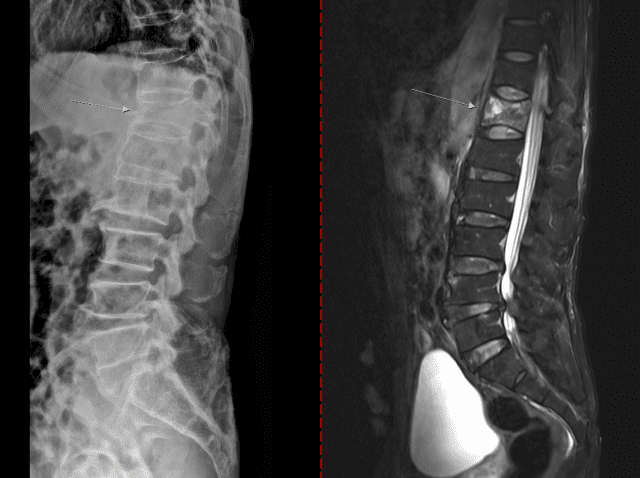

골다공증은 초기 통증이나 자각 증상이 거의 없다가 시간이 지나 가벼운 충격만으로도 손목이나 대퇴골(엉덩이뼈)이 골절되면서 뒤늦게 진단되기도 한다. 때로는 등이 굽거나 키가 줄어드는 척추 압박골절이 나타날 수도 있다.

치료 없이 방치하면 뼈는 점점 약해지고 척추와 손목, 대퇴골 골절 등이 발생할 수 있다. 대퇴골 골절은 고령 환자에서 수술 후 합병증, 장기 입원, 사망률 증가와 직결되는 중증질환이다. 척추 압박골절의 경우 자세 변화, 만성 통증, 보행 장애를 유발해 ▲활동량 감소 ▲근력 저하 ▲추가 골절의 악순환으로 이어진다.